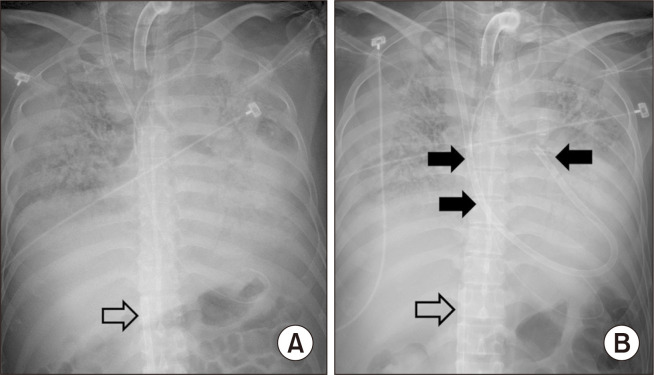

静脉体外膜氧合(VV ECMO)常用于严重呼吸衰竭的病例,尤其是考虑进行肺移植的患者。然而,由于许多肺部疾病最终会导致右心衰竭,当患者已经接受静脉体外膜肺氧合(VV ECMO)支持时,继发性右心衰竭的治疗可能会面临挑战。在这种情况下,可以使用氧合右心室辅助装置(OxyRVAD)。OxyRVAD 的设计旨在维持前向血流,防止右心室扩张。此外,肺动脉插管可经皮插入。我们报告了一例经皮 OxyRVAD 成功用于治疗呼吸衰竭患者右心衰竭的病例,患者当时正在接受 VV ECMO。

Venovenous extracorporeal membrane oxygenation (VV ECMO) is often used in cases of severe respiratory failure, especially in patients considered for lung transplantation. However, because many lung diseases can ultimately result in right heart failure, the treatment of secondary right heart failure can present a challenge when the patient is already under VV ECMO support. In such cases, an oxygenated-right ventricular assist device (OxyRVAD) can be used. OxyRVAD is designed to maintain anterograde blood flow and prevent right ventricular distension. Moreover, the pulmonary arterial cannula can be inserted percutaneously. We report a case in which percutaneous OxyRVAD was successfully implemented to manage right heart failure in a patient with respiratory failure who was on VV ECMO.